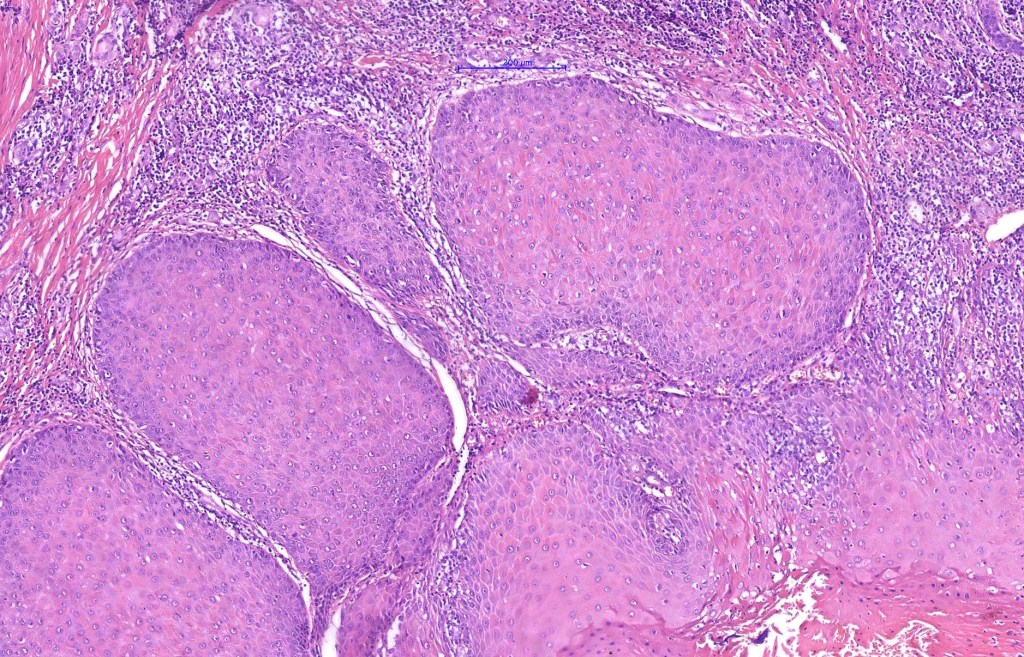

•Multilobulated cyst with associated lobules of well differentiated squamous epithelium

•+/- peripheral palisading

•Eosinophilic basement membrane